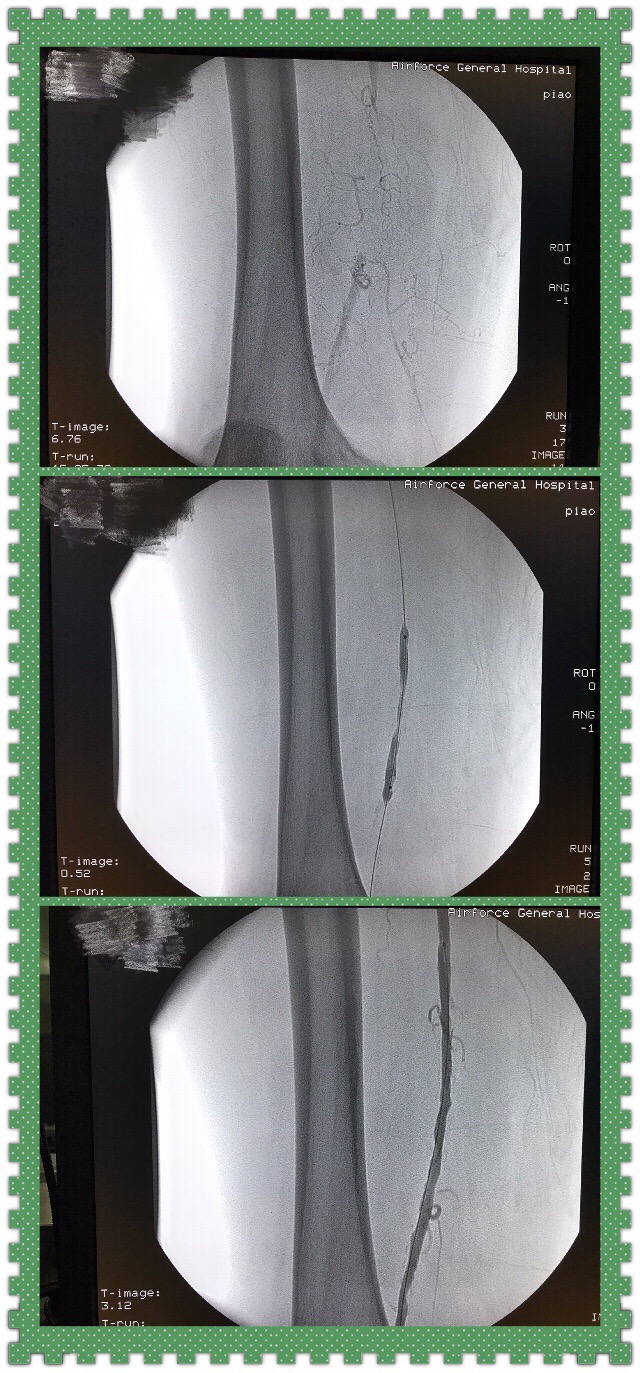

第三例患者是一位下肢动脉闭塞的病例。某部局级退休老干部,并且托关系找院领导关心,男性,70岁,由于没人照顾,我在寻找陪护和术中都"特殊关照"。病情需要我们对右股浅动脉进行了顺行穿刺,闭塞病变再通,可能手术时间短,仅20分钟,患者非常满意,就以为没什么事。为了安全,还对穿刺点强化包扎。本以为"高级″干部会有很好的依从性。可是,这个老同志躺不住,非常好客,几小时之后就下床接待客人,没过多会竞然消失了。最后发现在陪另一批客人花园散步。我不得不"抓一个"看似稳重的探视客人了解他是否有精神心理问题,答案是没有。老先生的回答令我们哭笑不得:"我认错,但我相信你的权威和技术″。对他,我只能冒着被告壮的风险对他威逼反脸。